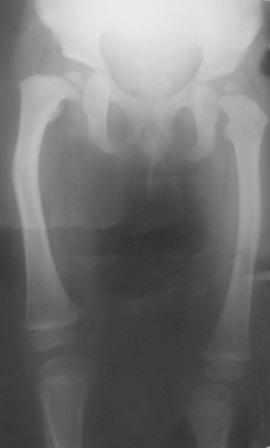

Варусная деформация бедра

Уважаемые коллеги. Осмотрена девочка 2007г.р. При рождении двухсторонная косолапость, двухсторонный врожденный вывых бедер, лечилась консервативно.

В данное время ходит самостоятельно, прихрамывает на прав.ногу, прав. нога укорочена на 3,5см и и находится в положении внутренней ротации 40гр. Леч.врач зав. кафедрой Т.О.мед. института.

Планируется подвертельная деротационно-вальгизирущая остеотомия бедра. Или остеотомия на верщине деформации бедра с удлинением по методу Илизарова.

Уважаемые ортопеды! Просим помочь по тактике лечения.